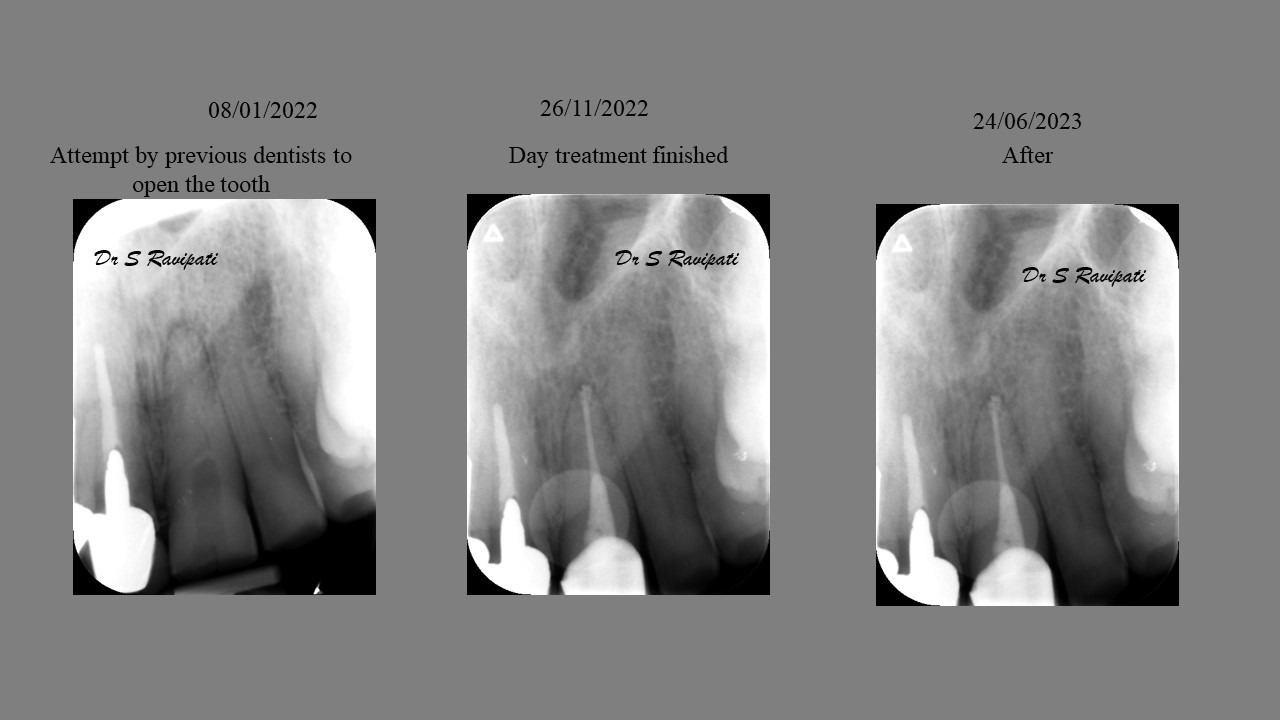

During the consultation, the dentist will first listen to your concerns and carry out appropriate tests to identify the right tooth that is causing pain. As a part of the diagnosis, your dentist will carry out various clinical tests to identify the right tooth and will take some radiographs which can aid in the diagnosis.

An access cavity is placed on the surface where the patient bites, to reach the root canals of the tooth. Once all the canals are identified, small files are used to remove the infected pulp.

Files of different sizes are used to eliminate bacteria and infection and to shape the canals. The canals are disinfected thoroughly with irrigants and later the canals will be sealed in 3 dimensions with a special medicament called gutta-percha to prevent reinfection of the tooth and the access cavity will be sealed with a temporary filling.

Studies have shown thorough cleaning with instruments, disinfection and sealing the canals contribute to the successful healing of the infection and this success is reported as 95%.